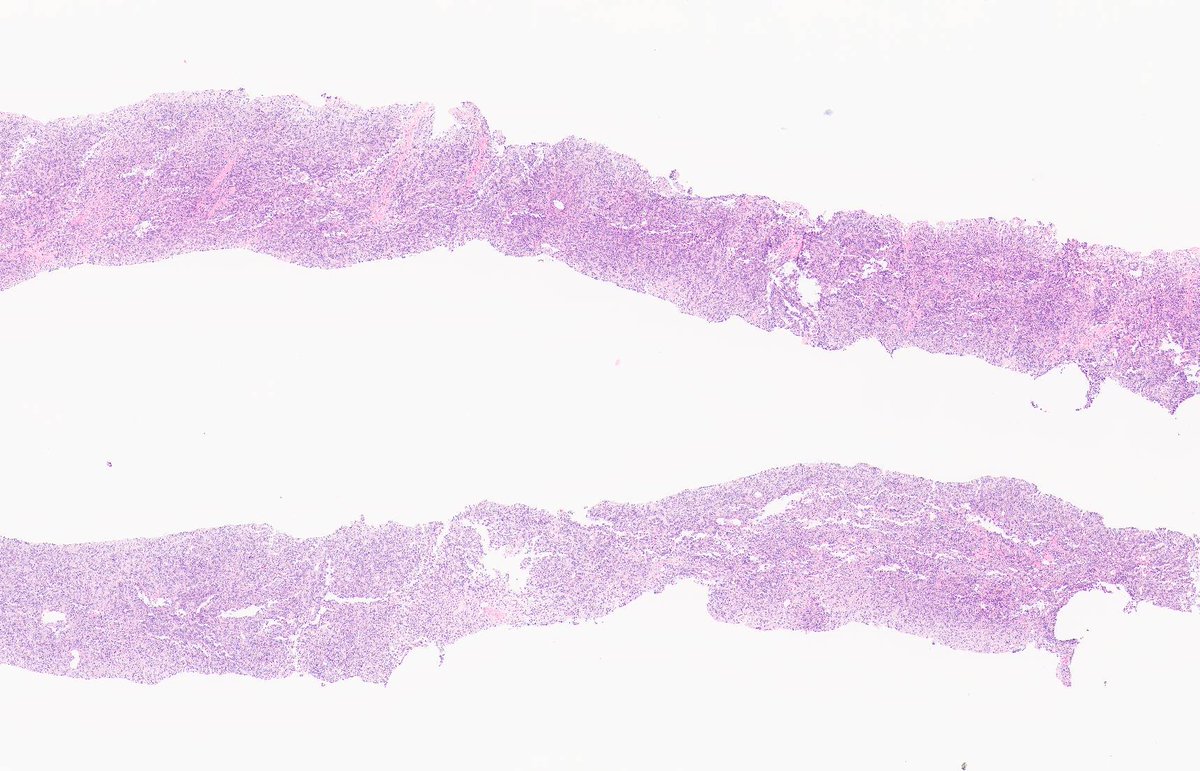

INTRANODAL PALISADED MYOFIBROBLASTOMA. IHC: SMA. NB: circumscribed with peripheral lymphocytic cuff; fascicles of spindle cells; bland nuclei with vague palisading; interstitial haemorrhage / haemosiderin; 'collagenous bodies' with variable mineralization.